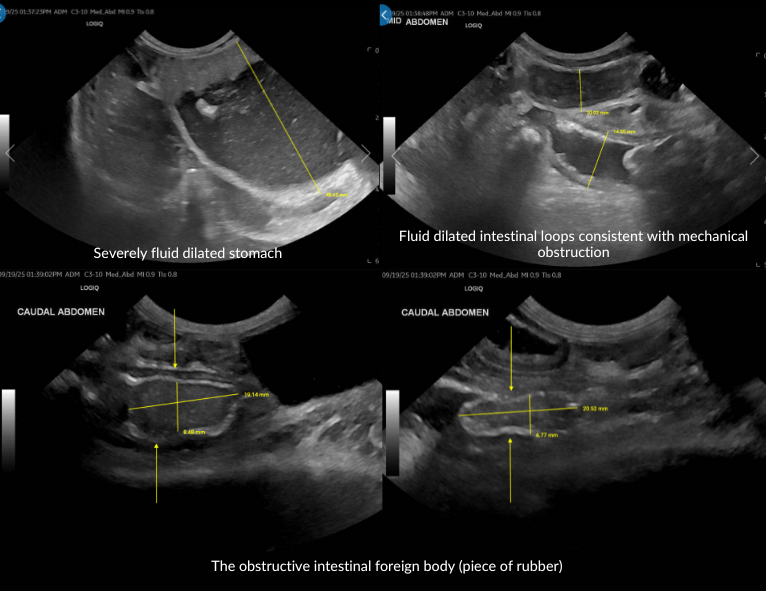

Within 1 hour, Dr. Kristin Welch, DACVECC, provided a STAT ultrasound interpretation. The scan revealed:

• Severe gastric distension with fluid measuring up to 71×48 mm

• Diffuse small-intestinal dilation (9–15 mm) with blurring of wall layering

• A distinct intraluminal echogenic structure (37×7 mm) consistent with mechanical obstruction

• Scant peritoneal effusion, likely secondary to intestinal compromise

While an intraluminal mass could not be entirely excluded, the imaging was most consistent with a jejunal foreign body obstruction. Immediate gastric decompression, fluid stabilization (especially potassium correction), and emergency exploratory surgery were advised.

Acting on the DVM STAT interpretation, the ER team proceeded with surgery. Intra-operatively, a rubber foreign body was identified and removed from the jejunum. Billy recovered uneventfully, regaining appetite and energy within days.